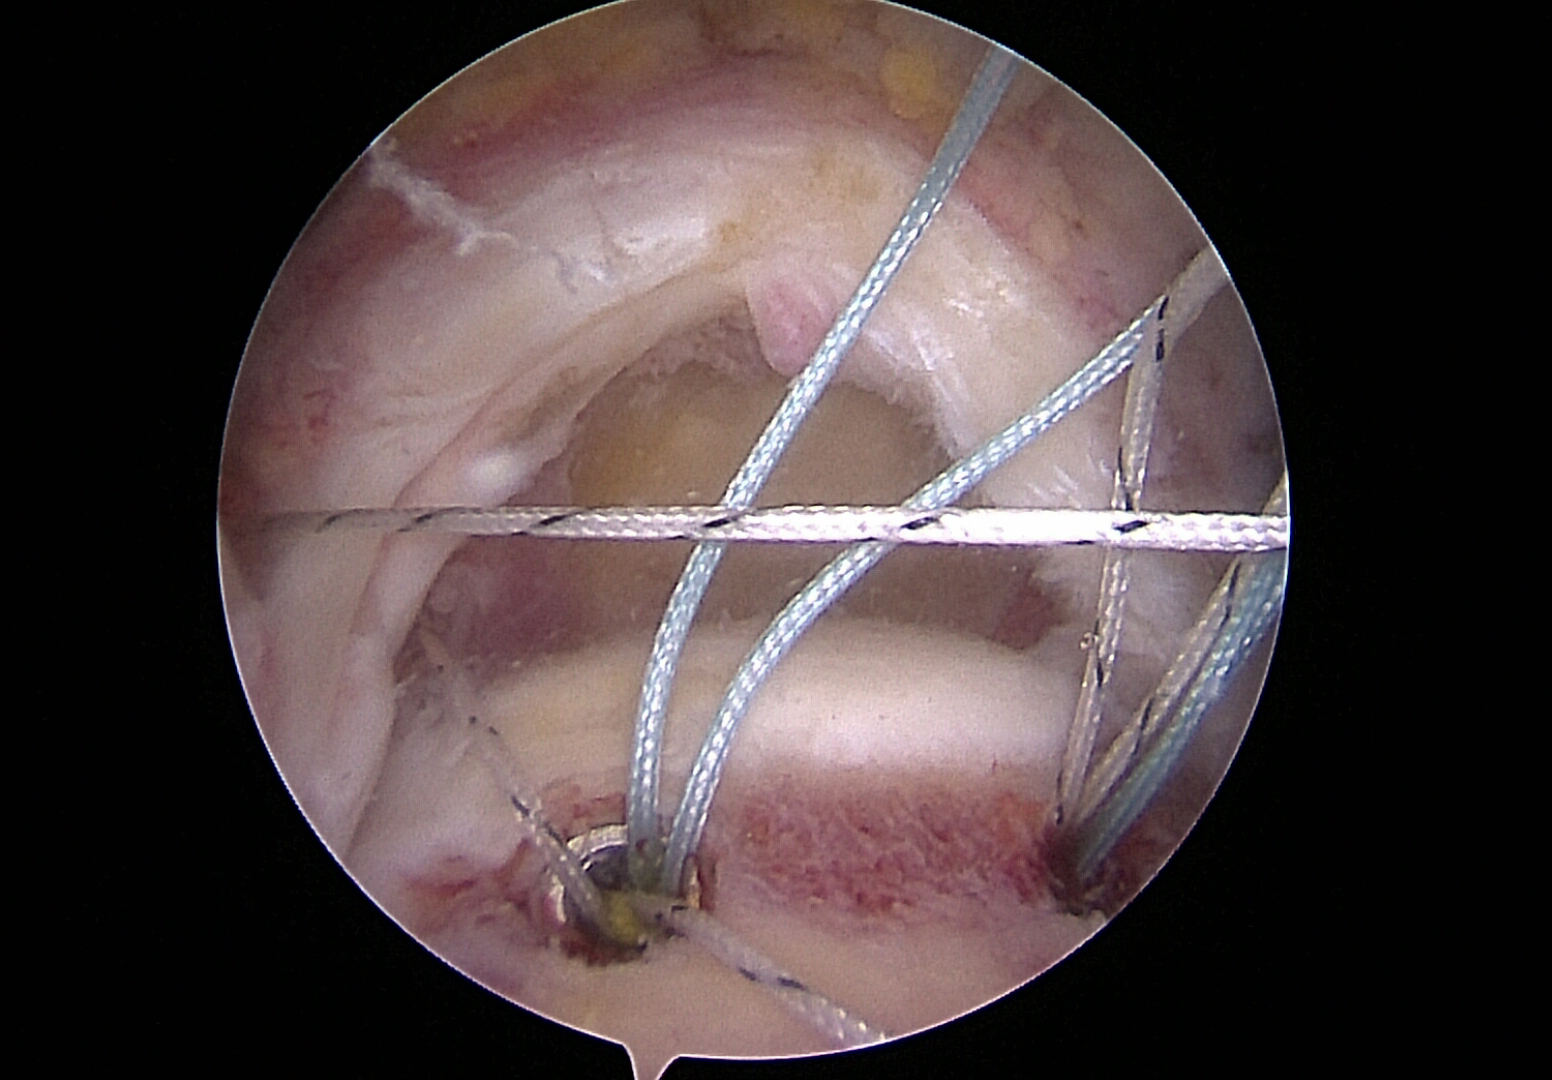

Vorgelegte Ankerfäden zur Rekonstruktion der Rotatorenmanschette

Ankerfäden durch Sehne vorgelegt zur Rekonstruktion